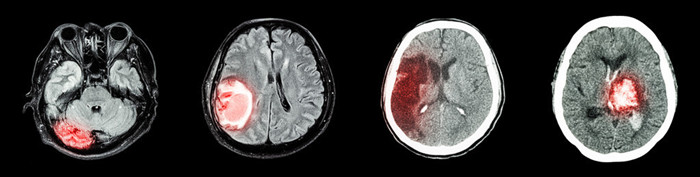

病例2:22岁小伙高血压脑出血

小杨22岁,高中毕业在家帮家里打点生意,20岁的时候就发现高血压,当时最高200/120mmHg,本打算吃药控制,可是有人在他耳边说,千万不能吃降压药,会伤肝伤肾,到时候找不到媳妇,要不了小孩。

结构22岁的时候,突发脑出血,及时送到医院,经过积极抢救,命救下了,可是给22岁的小杨内心深处留下了沉重的阴影。长期焦虑,怕自己哪天再发生脑出血,5年过去了,小杨依然没有女朋友。

高血压是导致脑出血最常见的原因,脑出血发生后会导致30-40%的人死亡。